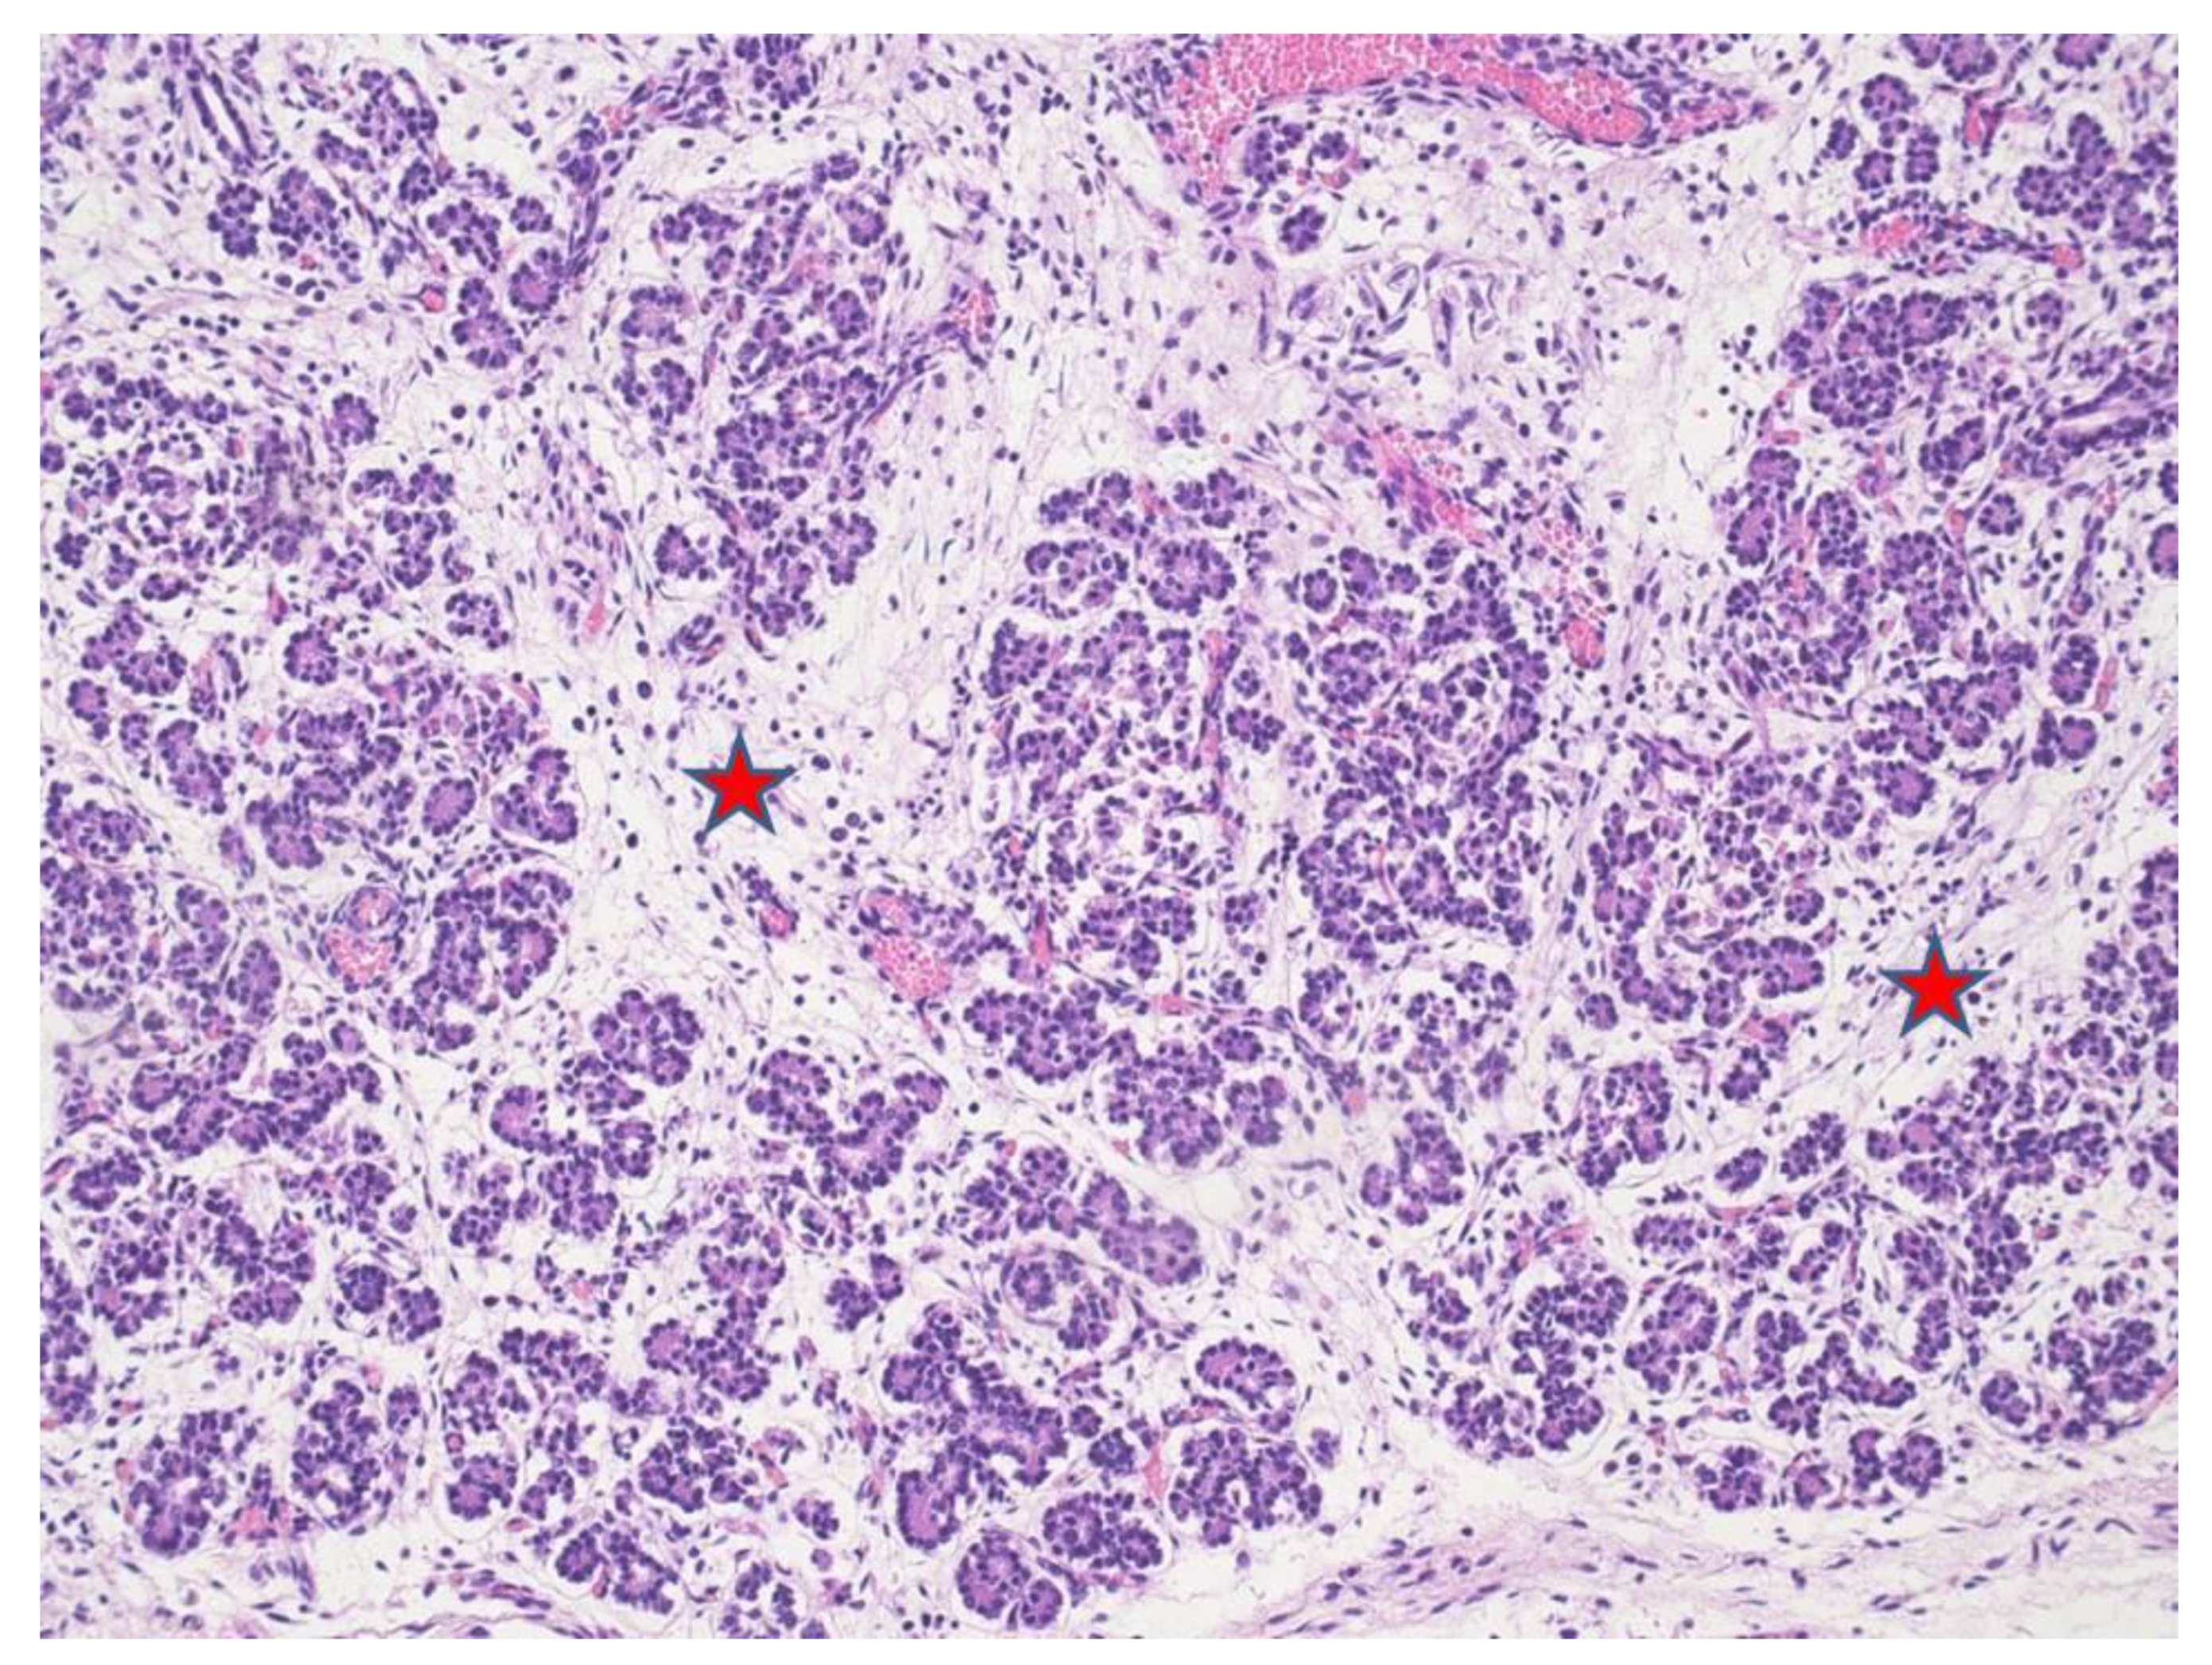

At microscopy, lungs displayed mild pneumonia with focal intra-alveolar neutrophils associated with rod-like bacteria (Figure 1). Neutrophils and rod-like bacteria were similarly observed in the lumen of the gastrointestinal tract (Figure 2). No other significant histological findings were noted except for mild pancreatic oedema (Figure 3).

Figure 3.

Pancreatic acini with interacinar edema (red stars) (HE staining 4×).